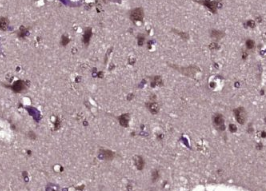

多聚甲醛固定,石蜡包埋(人脑胶质瘤);用柠檬酸钠缓冲液(pH6.0)煮沸15min后恢复抗原;用3%过氧化氢阻断内源性过氧化物酶20分钟;阻断缓冲液(正常山羊血清)在37℃下30min;用(B-RAF)多聚体抗体孵育。未结合的克隆抗体在1:400下在4°C下过夜,然后根据SP试剂盒(兔子)说明和DAB染色进行操作。